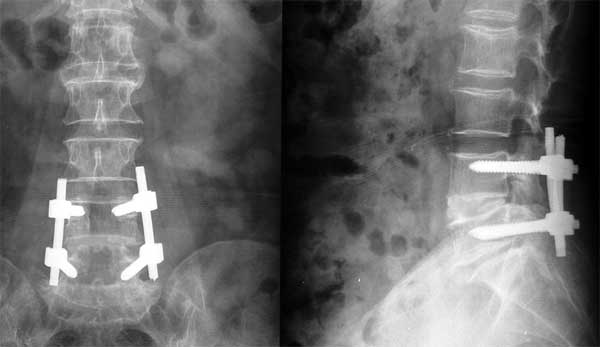

患者男性,腰椎4-5滑脱、退变,行内固定手术后椎间植入BMP, 术后6个月X线片显示椎体已融合。